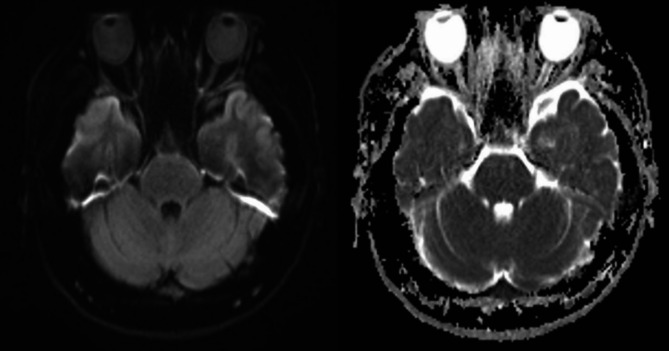

视网膜中央动脉闭塞是典型的与动脉粥样硬化性疾病相关的血栓栓塞现象。本病例报告描述了一例罕见的CRAO病例,年轻男性继发于高粘度综合征,作为混合表型急性白血病的第一症状。急诊医生必须认识到非典型的无痛性视力丧失的表现,并彻底评估这类患者,确保及时和视力保护干预。

Central retinal artery occlusion is typically a thromboembolic phenomenon associated with atherosclerotic disease. This case presentation describes a rare case of CRAO in a young male secondary to hyperviscosity syndrome as a first symptom ofMixed Phenotype Acute Leukaemia. It is imperative for emergency physicians to recognise an atypical presentation of painless vision loss and evaluate such patients thoroughly, ensuring timely and vision sparing interventions.